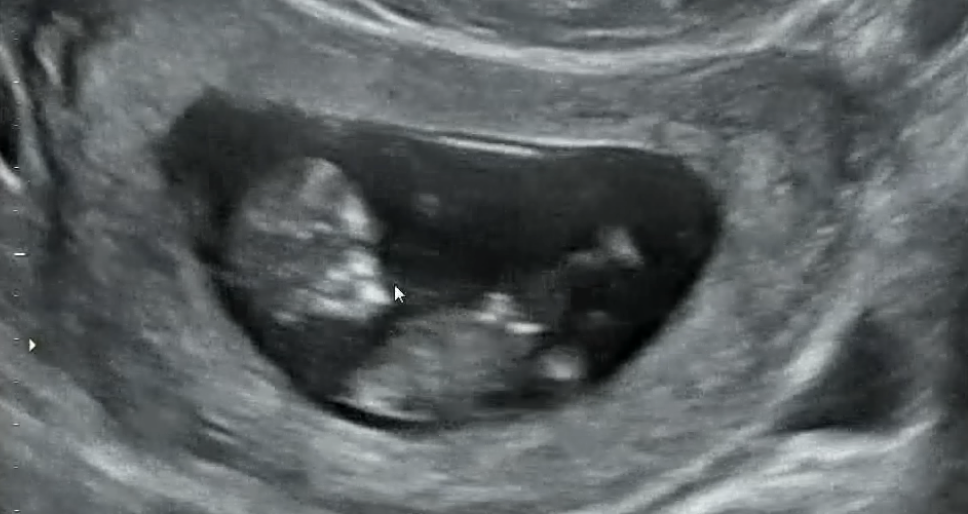

13주차 각도법 봐주세요~

좀 흐리긴 한데.. 너무 궁금하네요🥺

각도 볼 수 있는 사진이 아니에요~